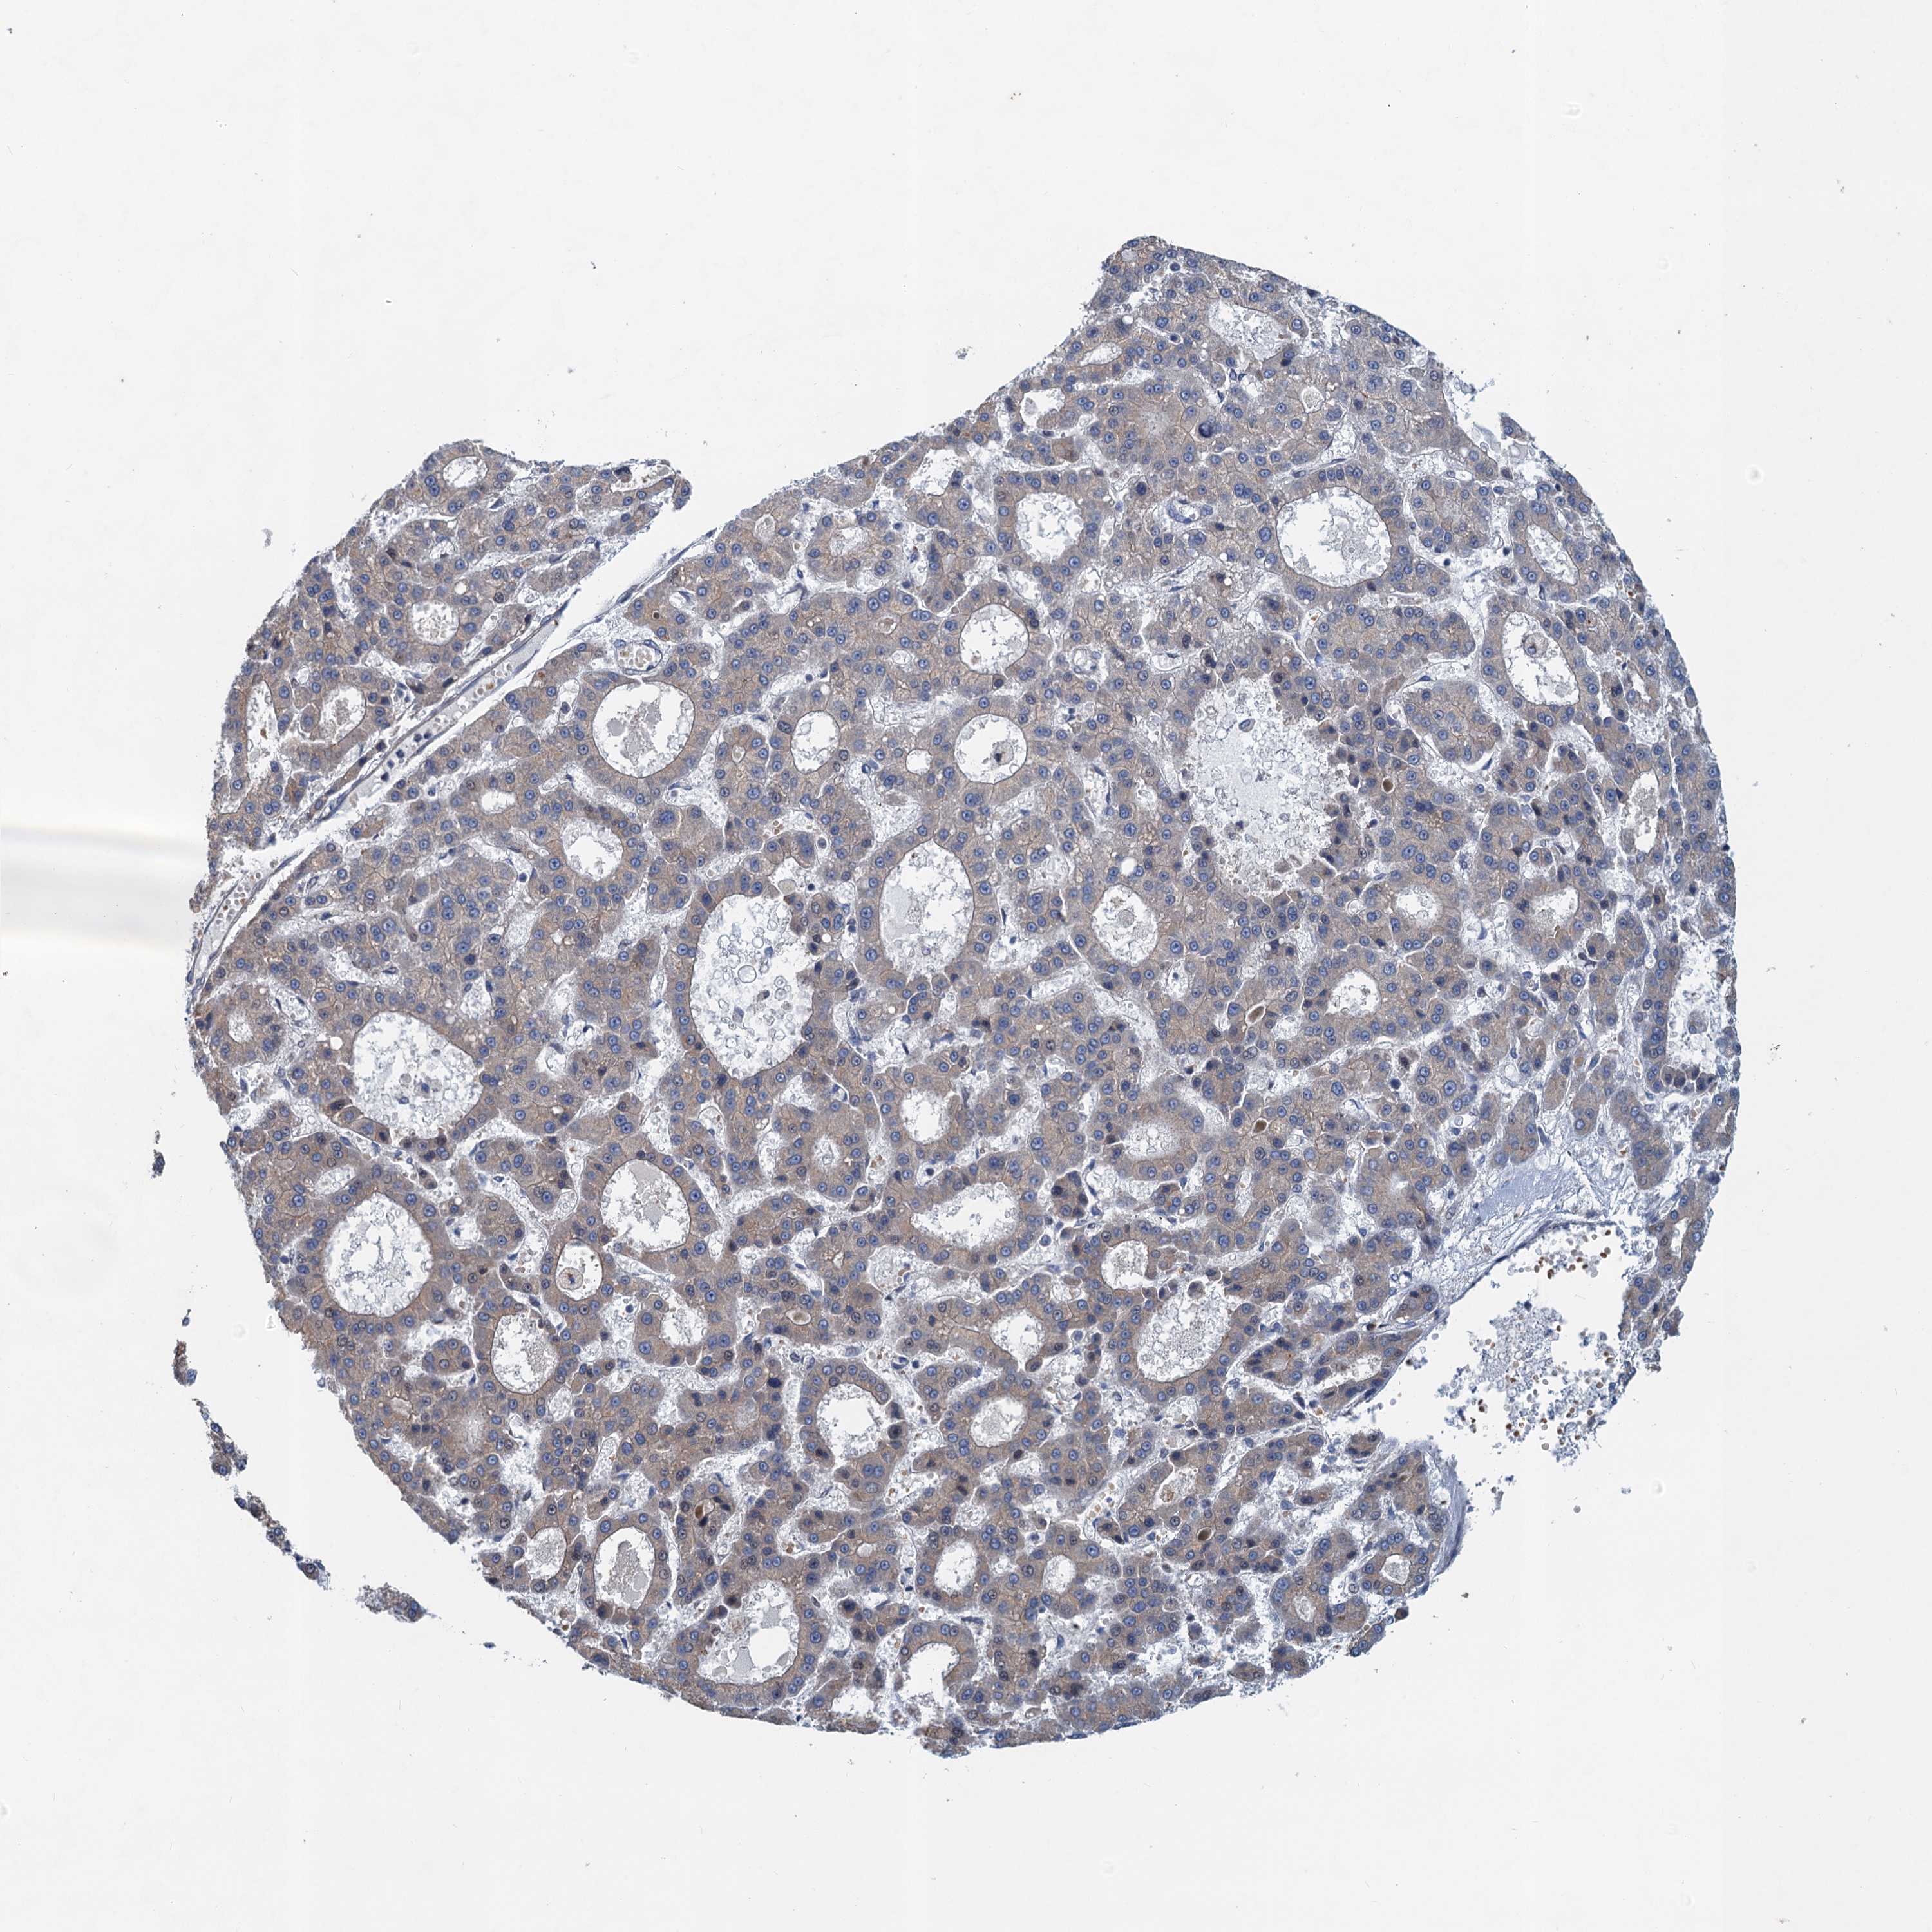

LIVER CANCER - Protein expressioni

A mouse-over function shows sample information and annotation data. Click on an image to view it in a full screen mode. Samples can be filtered based on level of antibody staining by selecting one or several of the following categories: high, medium, low and not detected. The assay and annotation is described here.

Note that samples used for immunohistochemistry by the Human Protein Atlas do not correspond to samples in the TCGA dataset.

Antibody stainingi

Antibody staining in the annotated cell types in the current human tissue is reported as not detected, low, medium, or high, based on conventional immunohistochemistry profiling in selected tissues. This score is based on the combination of the staining intensity and fraction of stained cells.

Each image is clickable and will lead to virtual microscopy that enables deeper exploration of all samples and also displays staining intensity scores, fraction scores and subcellular localization as well as patient and tissue information for each sample.

Antibody HPA039730

Antibody HPA040385

Staining

High

Medium

Low

Not detected

Intensity

Strong

Moderate

Weak

Negative

Quantity

>75%

75%-25%

<25%

None

Location

Nuclear

Cytoplasmic/membranous

Cytoplasmic/membranous,nuclear

Cholangiocarcinoma

Carcinoma, Hepatocellular, NOS